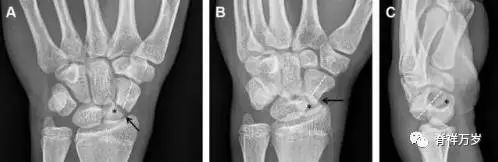

32.掌板骨折

掌板是掌指关节和指间关节关节囊掌侧的纤维结构,防止关节过伸。掌板的远端部是增厚的纤维软骨,附着于指骨掌侧基底部,而其两侧与侧副韧带的纤维融合。掌板骨折多发生于过伸损伤,为撕脱性骨折。

图 3 掌板骨折(A~C)小指前后位、斜位、侧位片,由于骨折的部位及特点,在前后位片上通常难以发现骨折;放大后的斜位(D)、侧位(E)可见一骨碎片(白色箭头)。

33.腕掌关节骨折脱位

腕掌关节骨折脱位为高能量损伤,常伴有神经损伤。腕掌关节组成骨多,侧位片上重叠遮挡多,骨折不易发现,容易漏诊。在前后位片上,关节面不平滑、关节间隙不对称、关节皮质破坏、关节面重叠常提示腕掌关节骨折脱位。特别是第 4、5 腕掌关节脱位,在前后位片上不容易发现;该损伤不稳定,也称为「变异型拳击手损伤/骨折」。

图 4 第 4、5 腕掌关节骨折脱位。(A)正常腕掌关节,关节面平衡起伏、平行;前后位(B)、斜位(C)、侧位(D),第 5 掌骨近端附近软组织肿胀(白色箭头),冠状面关节面重叠,背侧撞击剪切应力致钩状骨骨折(*),在前后位及斜位片上可见双密度影。第 4 掌骨底部可见微小骨折碎片(D,虚线箭头),第 4、5 掌骨掌侧成角。(E~G)变异型拳击手损伤:第 4、5 掌骨背侧脱位而未见骨折(E,虚线方框),钩状骨有骨折小碎片(F,短虚线箭头),第 4 掌骨基底部关节内骨折(G,长虚线箭头)。